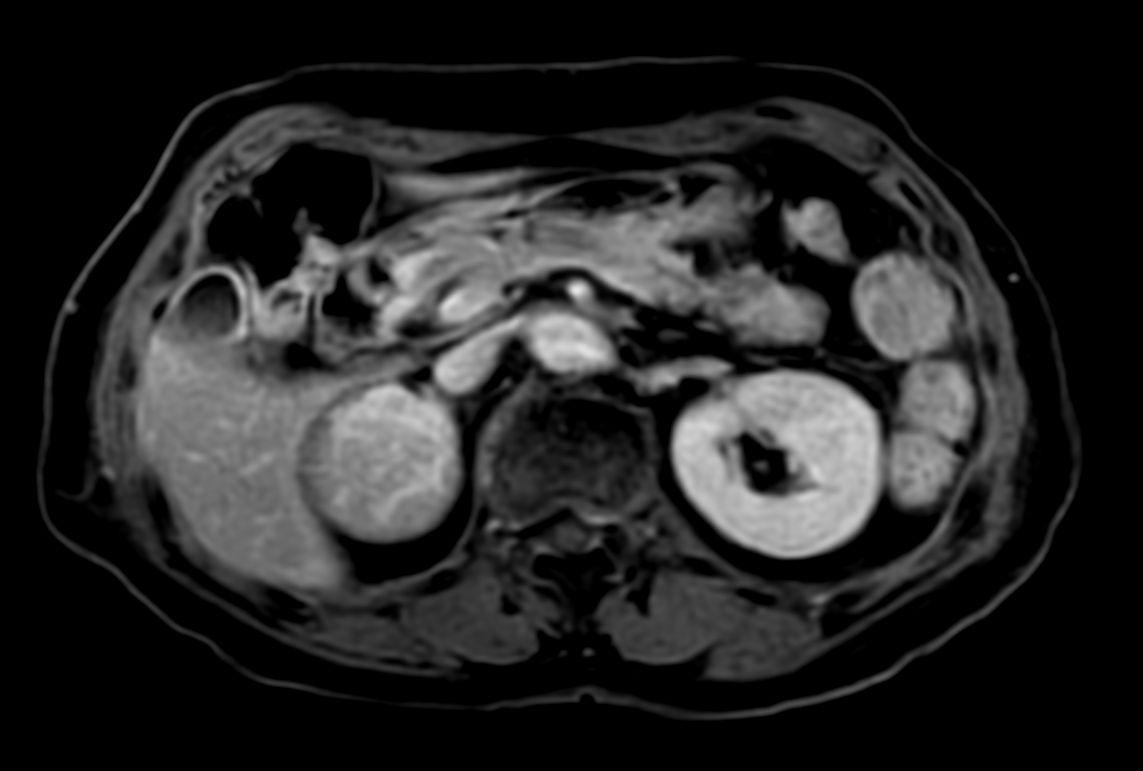

Patient with a kidney lesion. The ExamCard includes techniques for 3D imaging (PelvisVIEW, eTHRIVE) allowing for multiple image directions in one single scan, efficient fat-free imaging over large field-of-views (mDIXON XD), a multi-phase contrast-enhanced sequence (4D FreeBreathing) to improve imaging confidence and Compressed SENSE to accelerate the entire exam.

DWI b800